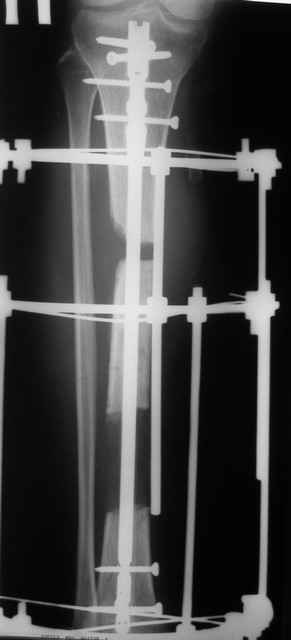

В июне 2009 года, при рассверливании канала произошел ожог передней стенки ББК. Со слов оперировавшего хирурга: «Не обратил внимания на то, что головка римера уперлась, и спохватился только в тот момент, когда прямо на глазах появилась яркая гиперемия кожи над этим местом». Никаких действий по этому поводу не предпринималось. (Интересно, а что можно было бы осуществить в таком случае?). Операция была закончена, пациент выписан. Вскоре образовался некроз, пациент лечился в стационаре. Попытка хирурга закрыть дефект ротационным кожным лоскутом не увенчалась успехом. Больной выписан.

Итак, в настоящий момент больной пришел к нам с полной нагрузкой на оперированную конечность и с такой картиной (см. приложение). Участок мягких тканей с передней стенкой нижней трети ББК, выгнил и представляет дефект 2×2,5 см. На перевязке - циркулярный(?) некроз костной трубки.

Пациенту за 70 лет. Мои соображения: 1 этап - резекция tibia + косая остеотомия fibula + «острое» укорочение + IM цемент-гвоздь с а/б + beads. 2 этап (по заживлению раны) – удаление цемент-гвоздя + (LATN) Lengthening and Then Nailing. Прошу помощи по тактике.Никита Заднепровский